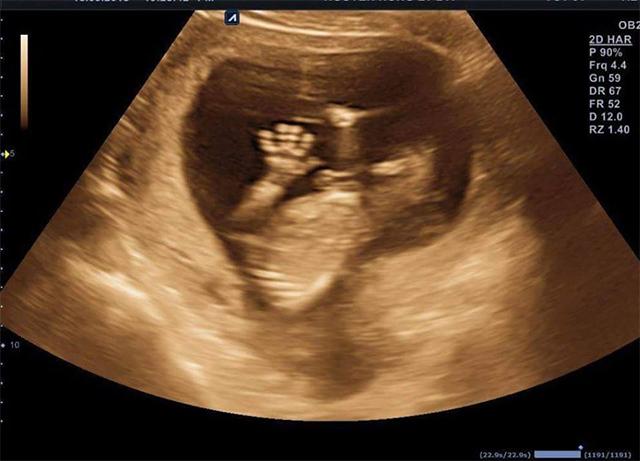

Liên lạc với chị Hồng Lý, chị cho biết đây không phải là hành động đáng yêu duy nhất mà con ra dấu hiệu với vợ chồng mình trong lúc siêu âm thai. Trước đó, em cũng từng giơ bàn tay xinh ra như chào bố mẹ khi siêu âm 15 tuần.

Ở tuần 15 thai kỳ, em bé nhà Hồng Lý giơ tay như chào bố mẹ.